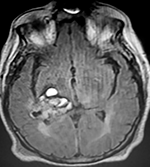

LA RMN muestra una lesión bien circunscrita frontal parasagital izquierda con edema perilesional, hiperintensa en T1 y T2, de contenido sólido y quístico, con poca captación del medio de contraste.

Se realizó craneotomía frontal para abordaje interhemisférico anterior.

Se realiza resección total de la lesión de contenido hemático oscuro-verdoso, consistente en un angioma cavernoso. La RMN postoperatoria se observa solo la brecha quirúrgica sin evidencia de lesión.

En el postquirúrgico el paciente desarrollo síndrome frontal lateral, que se controló con Risperidona y remitió después de tres semanas, las crisis convulsivas remitieron y el medicamento se disminuyó de manera paulatina (figs. 4 y 5).